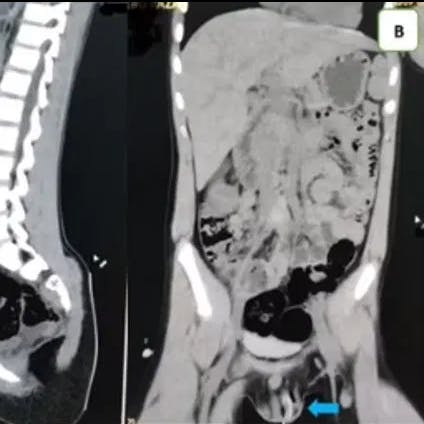

Ved hjælp af endoskopi slap lægerne for at åbne manden ved en operation, og de kunne fiske telefonen op i tre dele fra mandens bug.

Lægen Skender Teljaku har efterfølgende delt det usædvanlige fund på sin Facebook og oplyser i samme ombæring, at indgrebet foregik uden komplikationer.